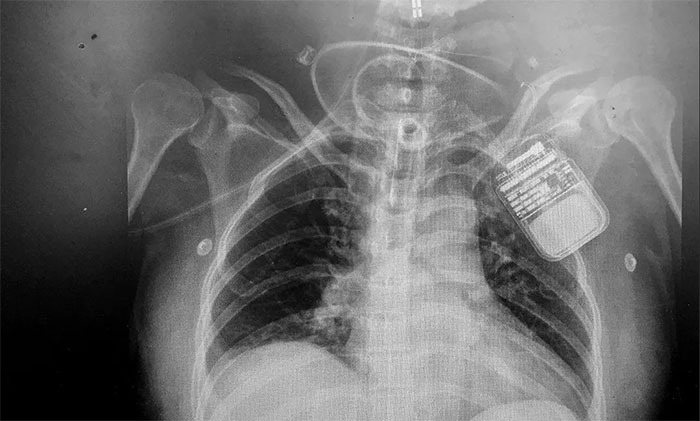

脊髓神經(jīng)電刺激術是通過微創(chuàng)手術將電極置入脊髓上方,以脈沖電流刺激脊髓神經(jīng),增加腦血流、腦代謝,而且還能激活腦干網(wǎng)狀上行系統(tǒng),這樣不僅能改善腦循環(huán)、縮小缺血灶,還能興奮大腦皮層,促進患者神志清醒。

該技術具有微創(chuàng)、可逆,并可依據(jù)患者病情需要進行治療參數(shù)的調(diào)節(jié),實現(xiàn)個體化定制,同時可有效改善患者全身循環(huán)水平等優(yōu)勢,幫助對長期昏迷特別是“植物人”促醒。

▲ 電刺激器順利置入患者脊髓上方